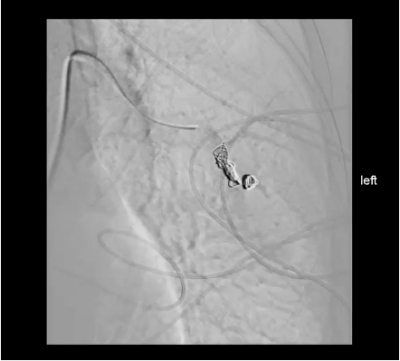

V prosinci 2023 byla pacientka poprvé hospitalizována na Interní hematologické a onkologické klinice FN Brno k realizaci uzávěru plicních AV malformací. V lokální anestezii byla pod ultrazvukovou kontrolou provedena punkce VFC vpravo a byl zaveden 6F sheath. Následně byl zaveden katétr cestou pravostranných srdečních oddílů do a. pulmonalis , kde byly provedeny opakované nástřiky kontrastní látky. Při nástřiku s katétrem centrálněji v a. pulmonalis se zobrazuje největší pAVM v S5, její odstup je ale obtížněji diferencovatelný a i přes opakované pokusy se nedaří zásobující větev selektivně nasondovat. Pro dlouhý čas byl výkon ukončen jako zmapování anatomických poměrů a odstupu přívodné tepny dominantní plicní AVM vlevo. Uzávěr zkratu byl naplánováns odstupem.Postupně byly v následujících třech sezeních během ledna, února a března 2024 realizovány uzávěry celkem šesti klinicky významných pAVM, převážně v cévním řečišti pravé plíce, s průměrem přívodné arterioly 3 a více milimetrů.

Výkony proběhly bez komplikací a pacientka je dále bez detekce dalších klinicky významných plicních zkratů(obr. 3, 4).